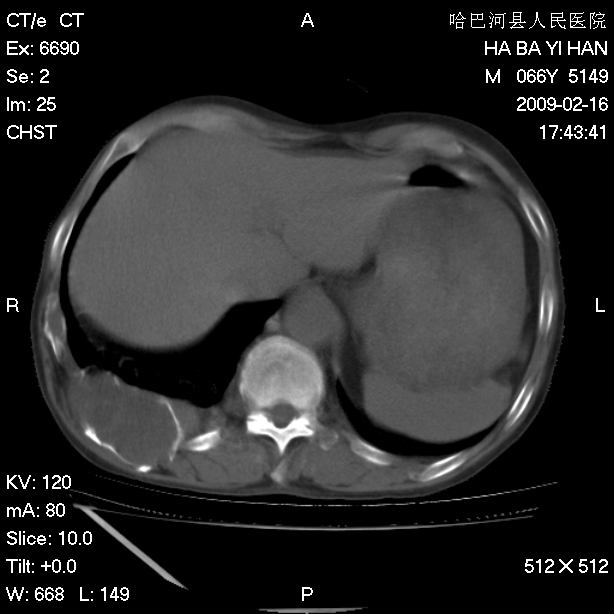

以下是引用huangxun4321在2009-2-16 20:18:00的发言:[br]部分病灶可见硬化边,部分可见骨质破坏消失,部分病灶内可见骨脊,说明病灶内既有良性病变,又有恶性病变,考虑骨巨细胞瘤恶变,未除骨纤恶变,畸形性骨炎少见,亦要考虑.

以下是引用731208在2009-2-16 20:31:00的发言:[br]考虑恶性胸膜间皮瘤并肋骨,脊柱转移。

以下是引用yijiansheng在2009-2-16 20:16:00的发言:[br]考虑恶性胸膜间皮瘤并肋骨,脊柱转移。

以下是引用形影不离在2009-2-16 19:55:00的发言:[br]考虑多发性转移瘤。